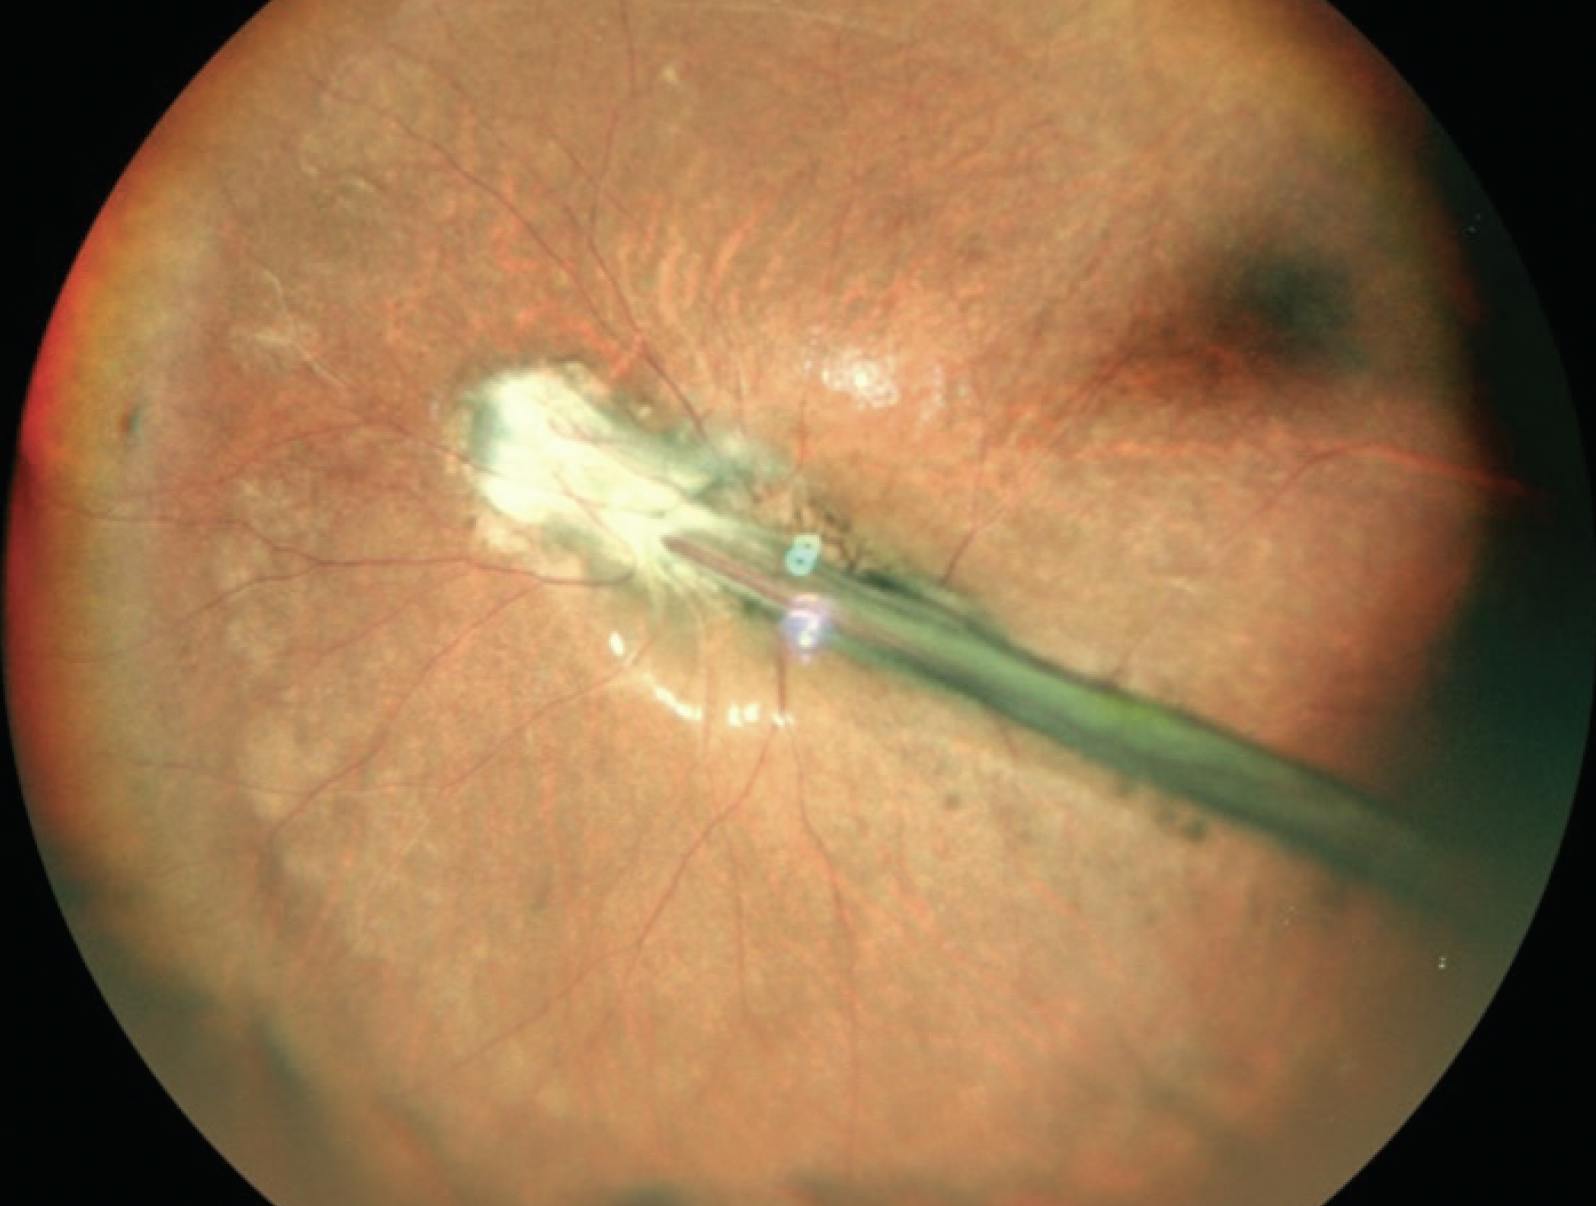

A 2.5-year-old boy presented with squinting in the left eye since birth. Dilated fundus examination revealed a fibrovascular stalk in the left eye extending from the disc to the posterior capsule of the lens suggestive of persistent hyperplastic primary vitreous (Figure 2). OCT showed an altered foveal contour. Ultrasound of the left eye showed membranous echoes with low to moderate spikes and restricted movements suggestive of persistent hyperplastic primary vitreous. The patient was advised to undergo refraction, use low vision aids, and follow up every 6 months.

<p>Figure 2. Widefield imaging of the left eye shows a fibrovascular stalk extending from the optic disc to the posterior capsule of the lens.</p>

Figure 2. Widefield imaging of the left eye shows a fibrovascular stalk extending from the optic disc to the posterior capsule of the lens.